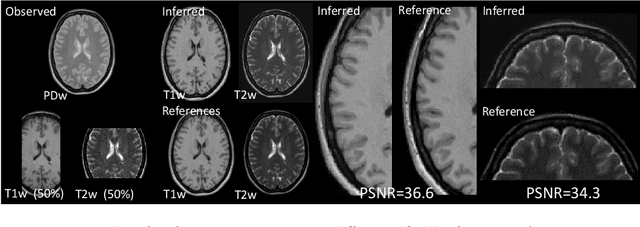

Automatically generating one medical imaging modality from another is known as medical image translation, and has numerous interesting applications. This paper presents an interpretable generative modelling approach to medical image translation. By allowing a common model for group-wise normalisation and segmentation of brain scans to handle missing data, the model allows for predicting entirely missing modalities from one, or a few, MR contrasts. Furthermore, the model can be trained on a fairly small number of subjects. The proposed model is validated on three clinically relevant scenarios. Results appear promising and show that a principled, probabilistic model of the relationship between multi-channel signal intensities can be used to infer missing modalities -- both MR contrasts and CT images.